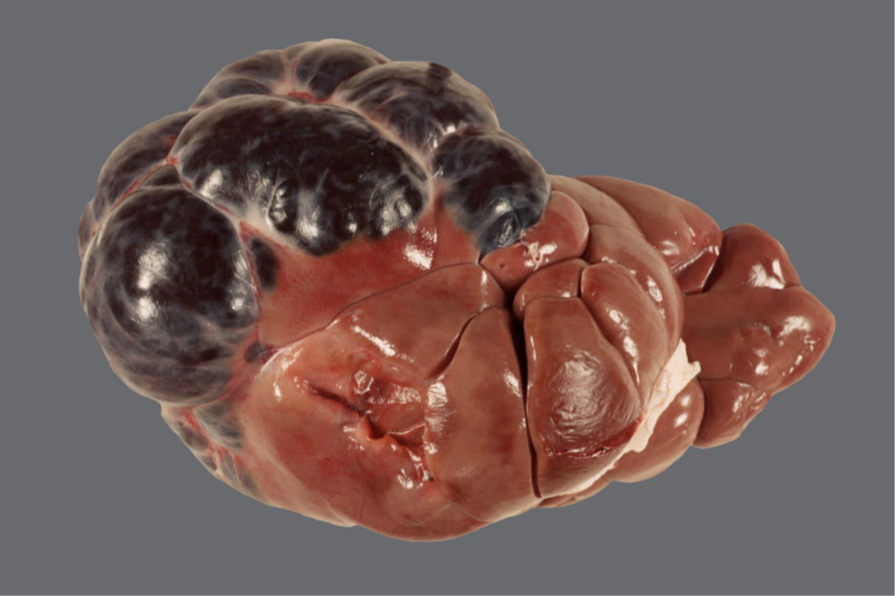

Schwein, Milz: Milztorsion mit hochgradiger, subakuter, diffuser hämorrhagischer Infarzierung

Milz

• Organ hochgradig geschwollen

• Bei Anschnitt Austritt einer roten, deckfarbenen Flüssigkeit (Blut)

• von Anteilen des großen Netzes umwickelt

Milztorsion mit hochgradiger, subakuter, diffuser

hämorrhagischer Infarzierung (sog. „Wickelmilz“)

Ventraler Anteil der Milz beim Schwein über das Lig. gastrolienale nur lose befestigt

→ Drehung des Organs um die eigene Längsachse um 180-240°

Venöser Abfluss beeinträchtigt bei anhaltender arterieller Blutzufuhr

→ lokale Kongestion → hämorrhagisches Ödem mit Diffusionsstörungen

→ Hypoxie sowie Gewebenekrose = hämorrhagische Infarzierung

Cave! ≠ hämorrhagischer Infarkt (Gefäßverschluss in Organen mit doppelter Blutversorgung →

Infarktgebiet eingeblutet)

Bei kompletter Drehung des Organs, die auch die arterielle Blutzufuhr unterbindet

→ Nekrose mit entzündlicher Demarkation, bindegewebiger Induration und Atrophie des Organs